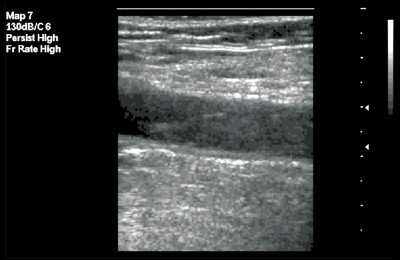

При аномалии размеров отмечалось нормальное расположение внутренней яремной вены и сонной артерии, однако диаметр внутренней яремной вены был меньше диаметра сонной артерии (рис. 4).

Рис. 4. Аномалия размера внутренней яремной вены при ее нормальном расположении (вена меньше сонной артерии и имеет округлый вид).